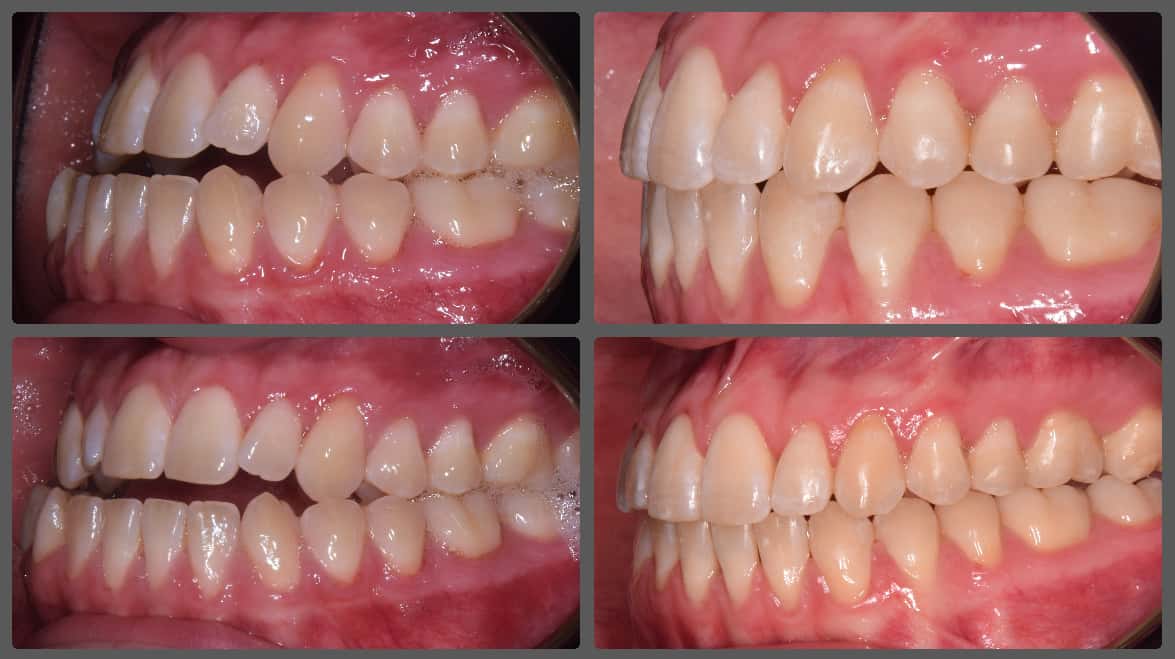

Balázs súlyos alsó torlódása miatt keresett fel magánrendelésemen. A diagnosztikus vizsgálatok során előbbin túl alsó-felső fogívszűkületet, valamint nyitott harapási hajlamot állapítottam meg. Kezelését Pitts21 alsó-felső rögzített fogszabályozó készülékkel kezdtük meg. A nyitott harapási hajlamot a hátsó fogakra helyezett harapásemelővel kontrolláltuk. A torlódott fogaknak tolórugóval és interproximális redukcióval teremtettünk helyet, és intermaxilláris gumihúzással tökéletesítettük a harapást. A fogszabályzó kezelés teljes időtartama alatt Balázs 110%-osan együttműködő volt, ezért 21 hónap alatt sikerült kiemelkedő végeredményt elérnünk.